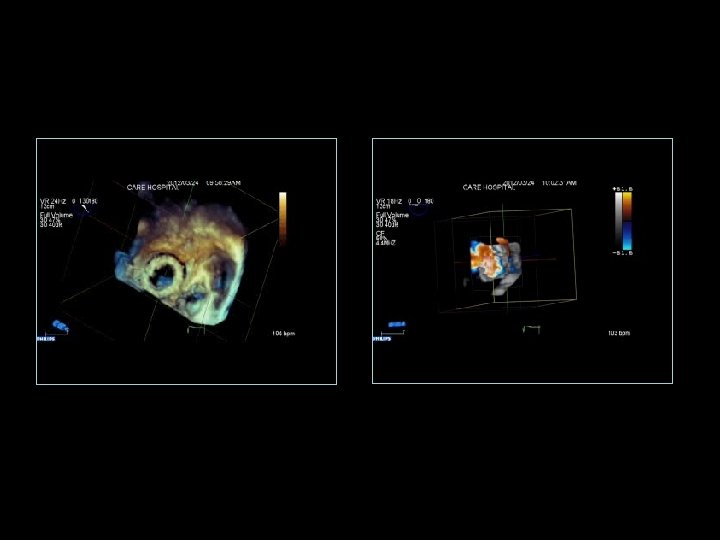

Anjali Bhattacharya MVR ( Tilting disc) Pro Valve dysfunction Pre and Post Lytic (Rx)